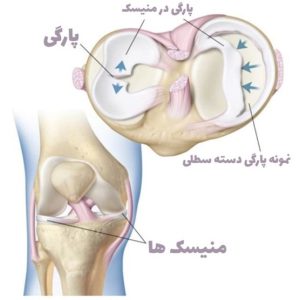

تصویر شماره یک (مقایسه منیسک سالم و آسیب دیده)

تصویر شماره دو ( پارگی منیسک)

منیسک ساختاری غضروف مانند (به بافت غضروف شبیه اما به مراتب از آن محکم تر می باشند)از جنس فیبری غضروفی (فیبروکارتیلاژ) در زانو است که به مفصل زانو ثبات می بخشد و منیسک زانو به عنوان ضربه گیر عمل می کند و از استخوان ها در برابر سایش و پارگی محافظت می کند. هر یک از زانوهای شما دارای دو تکه از این ساختارغضروف مانند است که بین کندیل های استخوان فمور ( ران ) و تیبیا ( درشت نی در ساق پا ) مانند بالشتک (بدلیل خاصیت ارتجاعی) قرار گرفته است :

- منیسک داخلی در قسمت داخلی زانو قرار دارد. (به شکل سی C لاتین)

- منیسک جانبی در قسمت بیرونی زانو قرار دارد. (به شکل او O لاتین)

- ظاهر مینیسک ها در مقطع زانو مثلثی شکل بوده .

- منیسک زانو ضخامتی در حدود ۶ تا ۸ میلی متر دارد.

- تغذیه منیسک در قسمت مرکزی ازطریق انتشار و در قسمتهای محیطی آن از طریق عروق خونی می باشد.